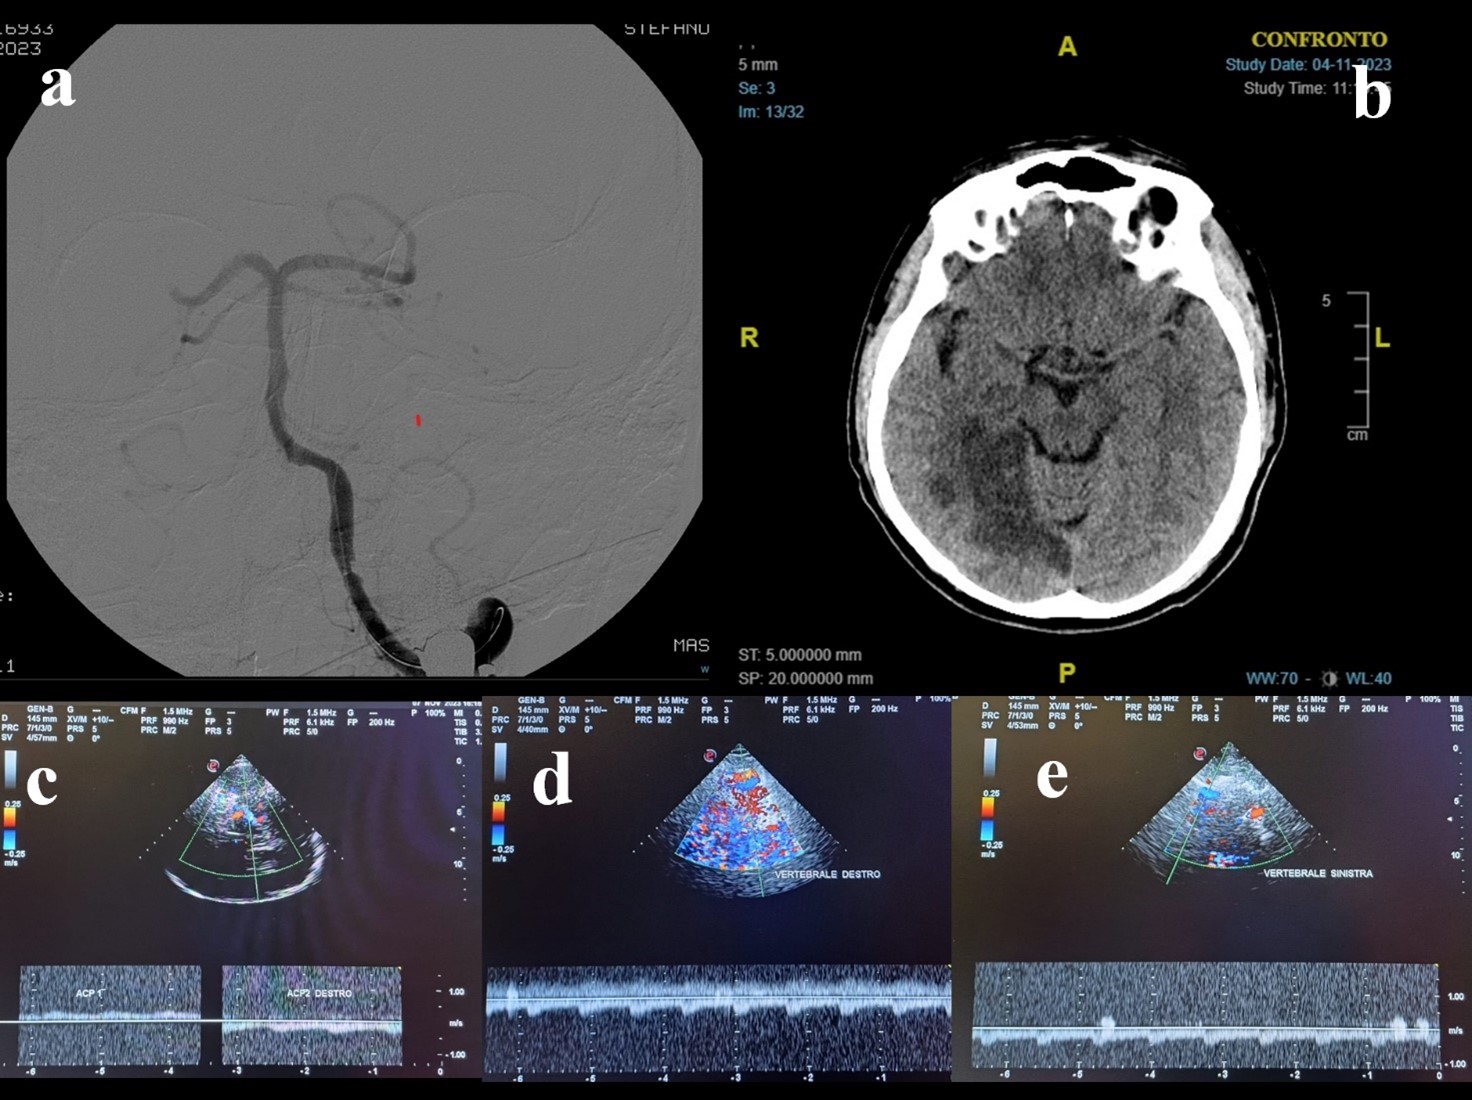

Figure 3. A 79-year-old Caucasian man awoke with right deviation of the head and right hemiparesis. His last known normal was 10 p.m. the previous night. His past medical history revealed arterial hypertension, diabetes mellitus, and dislypidemia. The patient was presented to the emergency department at 09:00 a.m. The neurological examination showed coniugate left gaze palsy, dysarthria, and right hemiparesis, with a fluctuating course. Urgent Head CT did not show acute lesions and the CT perfusion documented an area of ischemic core in the left pons (a) and penumbra in pons, medulla and bilateral superior cerebellar hemispheres (a,b). CTA documented distal basilar artery stenosis. The patient underwent urgent MRI which confirmed a right paramedian pontine DWI hyperintensity, in the context of which a moderate hyperintensity on FLAIR sequences was observed (c,d). Although basilar artery was associated with brainstem hypoperfusion, the FLAIR-positive lesion determined a significant risk for hemorrhagic transformation in case of revascularization. Hence, TCCS was performed and did not reveal hemodynamic demodulation in the proximal tract (f) and in the top (g) of basilar artery. Thus, DSA and PTAS were avoided. Dual antiplatet therapy was administered. In the following days the patient showed a gradual progressive improvement, with the evidence on a small lesion on control head CT (h).

Figure 4. A 68-year-old man presented to the emergency department because of a 4-days-history of brief recurrent episodes of dizziness, nausea, vomiting, and sweating. He suffered from arterial hypertension, diabetes mellitus, and he had a spontaneous subarachnoid hemorrhage 4 years before. He was taking clopidogrel. During the episodes described before, the blood glucose was normal. The initial neurological examination did not show any abnormal findings. The brain CT scan and ORL examination were unremarkable. The brain MRI showed DWI-(a) and FLAIR-(b) positive lesion in the right cerebellar hemisphere, without hypointensities in SWI (c). CTA revealed stenosis at the middle portion of basilar artery (d), that was confirmed by DSA (e). TCCS was performed and pointed out basilar artery hemodynamics within normal range (f). In light of this, stenting was not performed. The 24-hours control head CT confirmed the right cerebellar region, without signs of further expansion of the ischaemic area or hemorrhage (g). The best medical treatment was adopted. The patient showed a progressive clinical improvement.